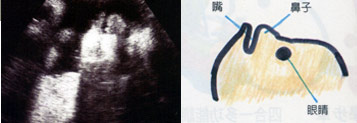

怀孕30周

怀孕30周

这张超音波照可以清楚的看到胎儿的眼窝、眼皮,还有嘴唇。